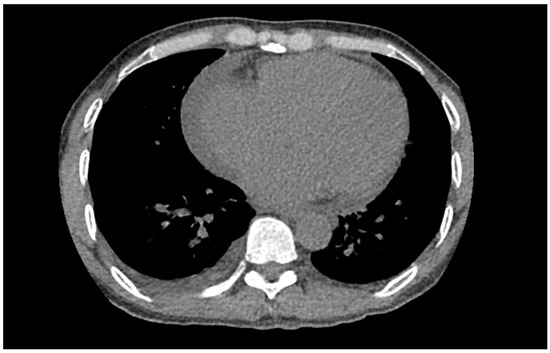

The patient’s EKG (Figure 1) on admission demonstrated a left bundle branch block pattern not previously documented in the patient’s medical history. Additionally, chest radiography (Figure 2) and computed tomography (Figure 3) on admission demonstrated cardiomegaly. Transthoracic echocardiography was technically difficult but demonstrated severe left ventricular systolic dysfunction with an ejection fraction of <15%. Initial brain natriuretic peptide (BNP) on admission was 981 pg/mL. The patient was recommended to start on 25 mg metoprolol succinate, 81 mg aspirin, 5 mg Lisinopril, and 40 mg atorvastatin. Metoprolol and Lisinopril were started initially as therapy for newly diagnosed DCM whereas aspirin and atorvastatin were started before coronary artery disease was ruled out with cardiac CT angiography (Figure 4 and Figure 5). The patient developed electrolyte abnormalities after the first day of treatment, including hypomagnesemia and hyperkalemia, likely secondary to longstanding untreated fluid overload due to heart failure. In response to this and the noted acute kidney injury, Lisinopril was discontinued. Additionally, the patient’s ALT and AST levels rose dramatically. Gastroenterology evaluation was obtained due to elevated liver function tests with a differential diagnosis of shock liver vs. Budd Chiari syndrome; therefore, N-Acetyl cysteine was prophylactically used and improved liver function over the subsequent week and atorvastatin was discontinued. The patient was continued on heart failure management. A repeat echocardiogram showed an improved ejection fraction of 25% with left ventricular dilation (left ventricular internal dimension in diastole 5.65 cm; left ventricular internal dimension in systole 4.95 cm; relative wall thickness 0.34; left ventricular mass 218.2 g; left ventricular mass index 131.8 g/m2) and no left ventricular thrombus noted. Additionally, mildly reduced right ventricular systolic function was noted.

Figure 3. Segment of computed tomography (CT) of the thorax demonstrating cardiomegaly.